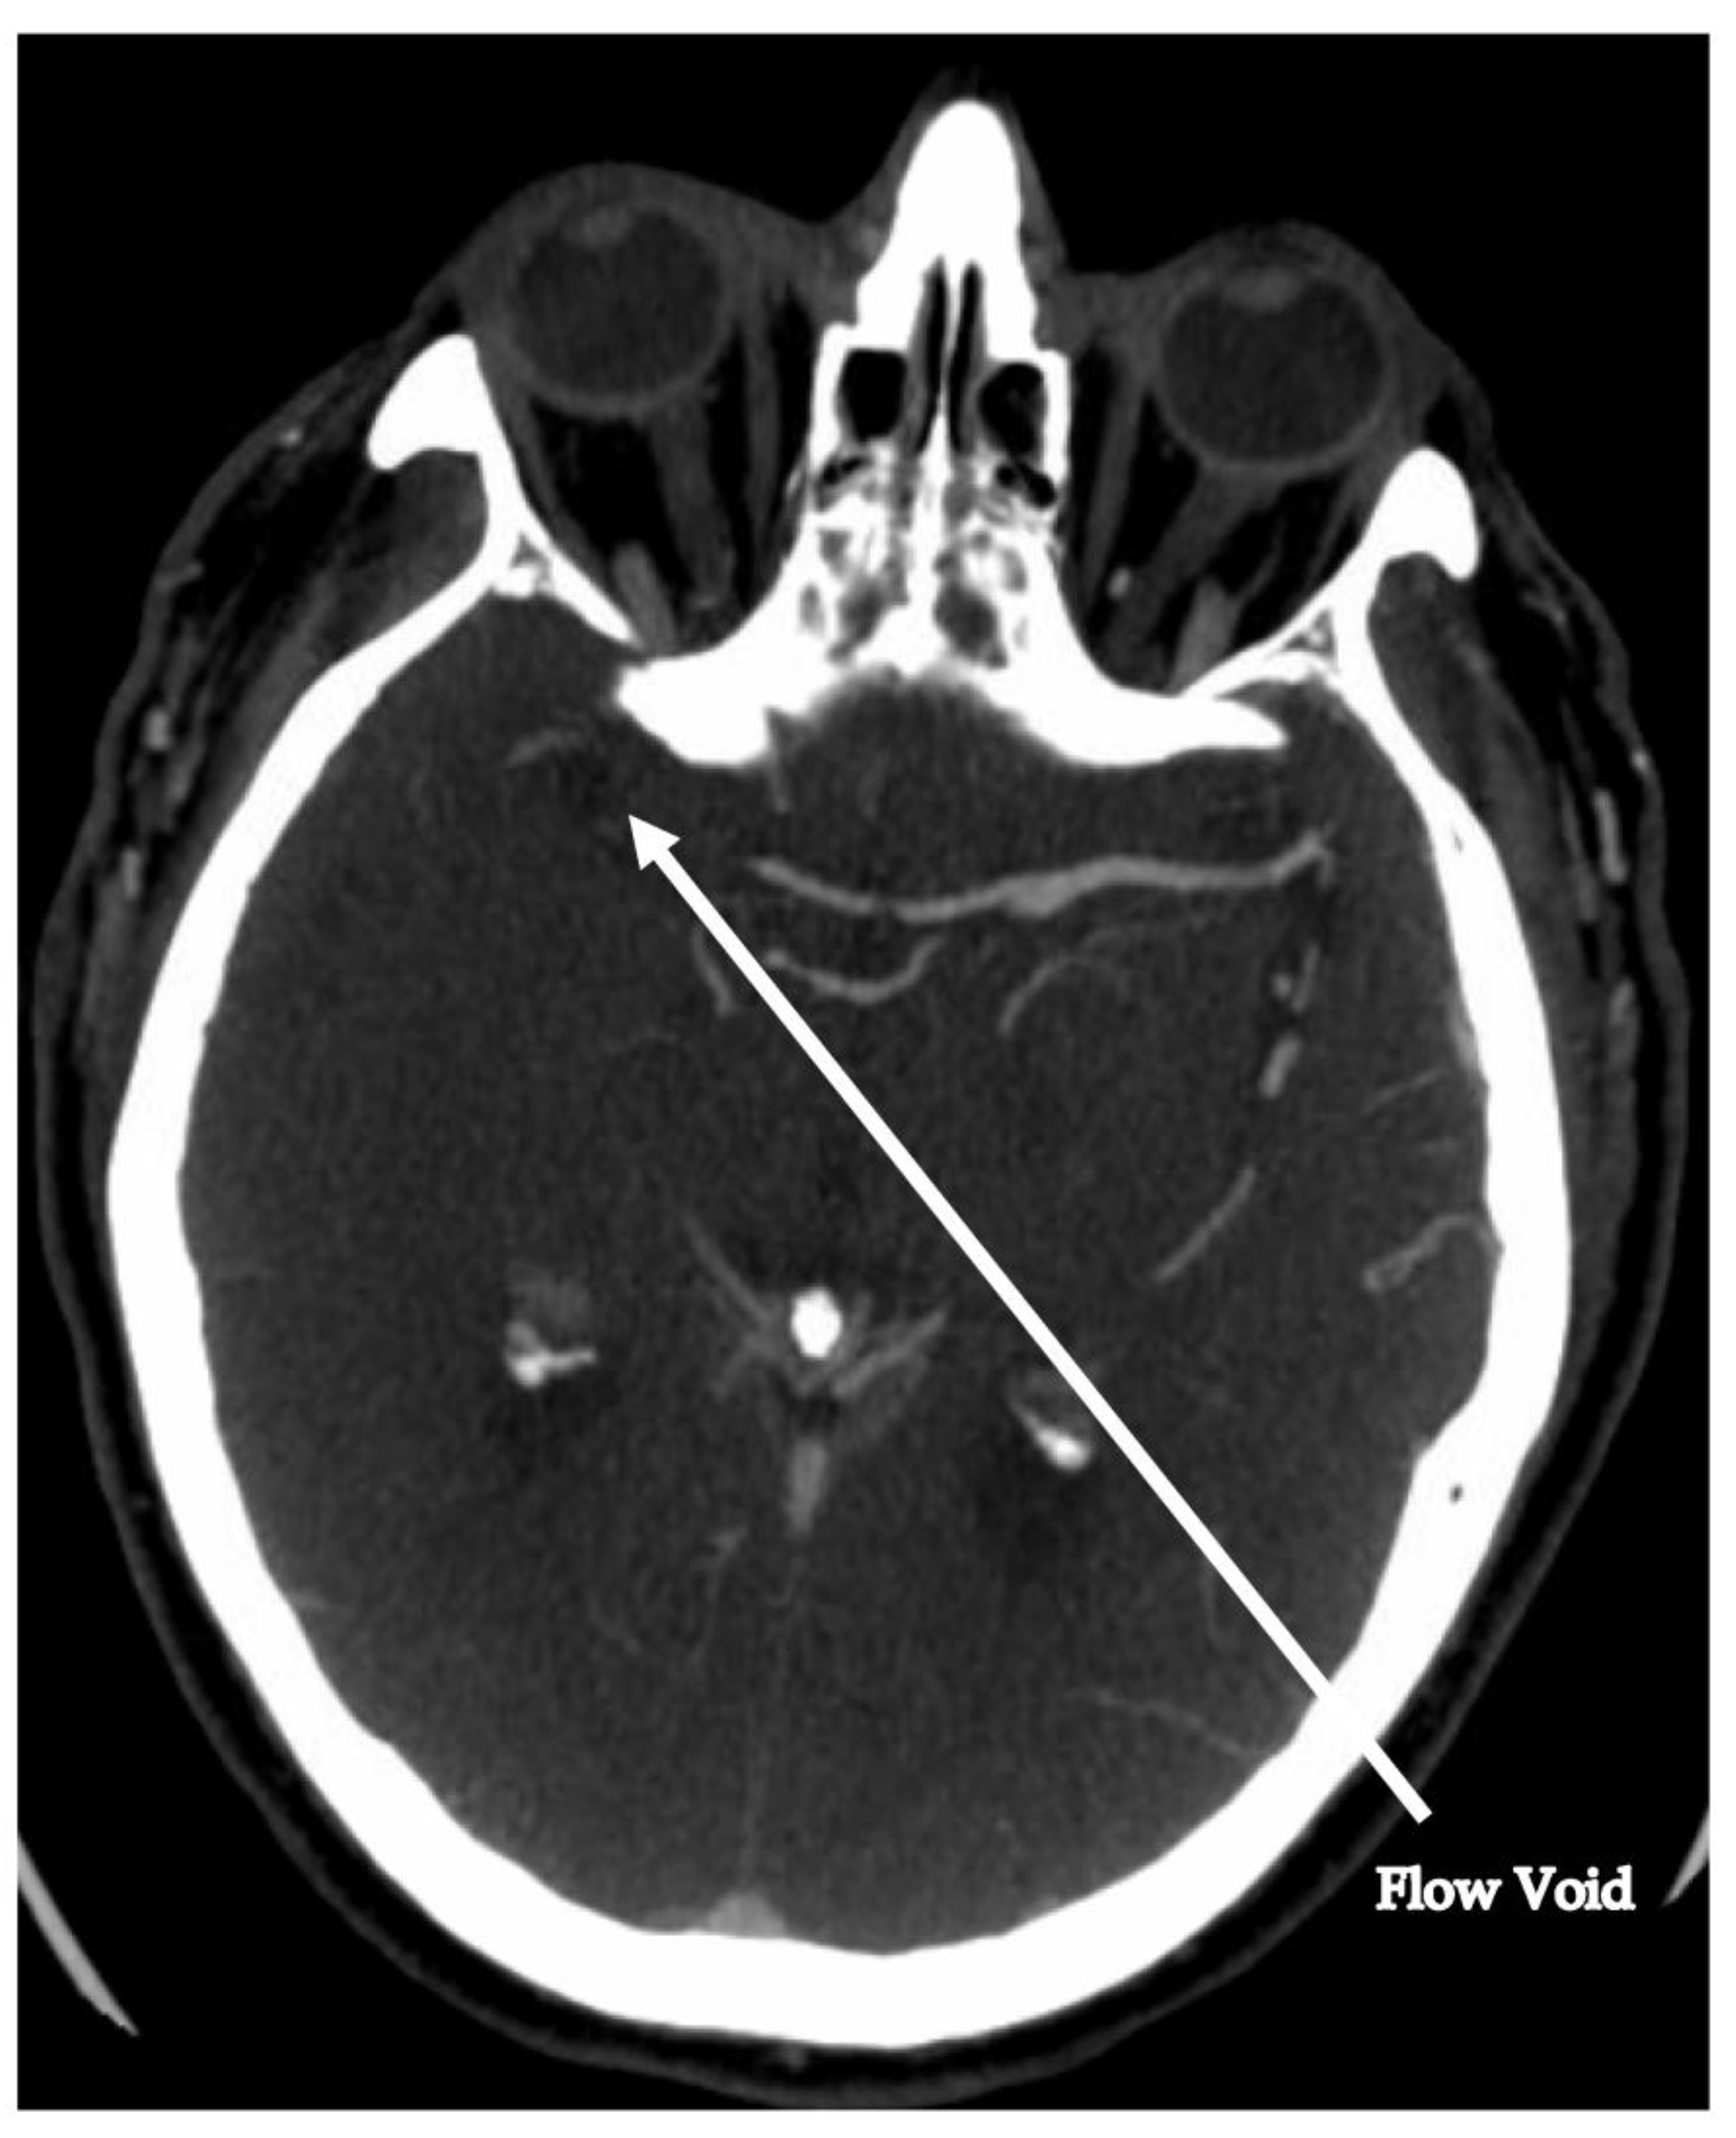

2. Case